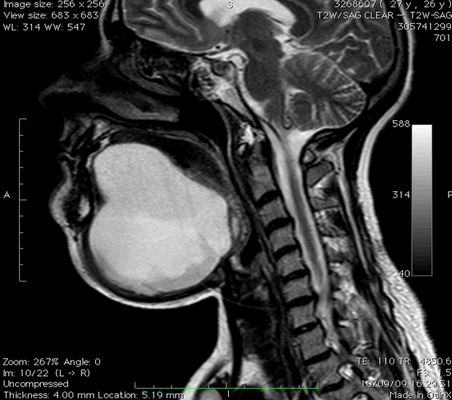

МРТ мягких тканей шеи что показывает

Воспалительные заболевания и объемные образования шеи часто встречаются в хирургической практике. Дифференциация патологий вызывает трудности из-за сложной анатомии рассматриваемой области и схожести клинических проявлений. МРТ позволяет получить подробные изображения мягкотканных и костных структур, опираясь на принцип магнитного резонанса. Компьютерная программа преобразует данные в серию срезов и формирует объемную картинку, которую можно увеличивать и рассматривать в любой плоскости. Толщину среза устанавливает врач в зависимости от предполагаемого диагноза, целей и задач исследования.

Для улучшения возможностей визуализации используют внутривенное введение контраста на основе хелатов редкоземельного металла гадолиния.

Магнитно-резонансная томография указанной области, вариант нормы

Что показывает МРТ мягких тканей шеи? На снимках видны:

добро- и злокачественные опухоли;

сосудистые мальформации, стеноз/дилатация артерий и вен, тромбообразование, отложение атеросклеротических бляшек;

лимфаденопатии при метастазах и воспалительной патологии;

ущемление нервных стволов;

послеоперационные осложнения и пр.